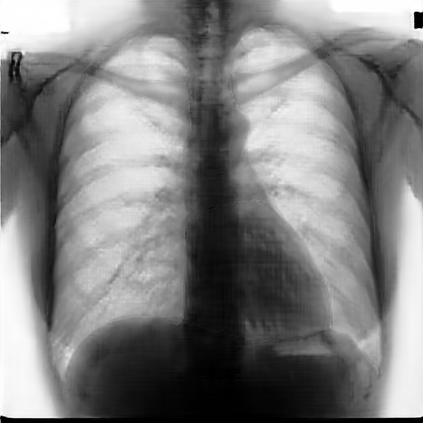

Multi-organ segmentation of X-ray images is of fundamental importance for computer aided diagnosis systems. However, the most advanced semantic segmentation methods rely on deep learning and require a huge amount of labeled images, which are rarely available due to both the high cost of human resources and the time required for labeling. In this paper, we present a novel multi-stage generation algorithm based on Generative Adversarial Networks (GANs) that can produce synthetic images along with their semantic labels and can be used for data augmentation. The main feature of the method is that, unlike other approaches, generation occurs in several stages, which simplifies the procedure and allows it to be used on very small datasets. The method has been evaluated on the segmentation of chest radiographic images, showing promising results. The multistage approach achieves state-of-the-art and, when very few images are used to train the GANs, outperforms the corresponding single-stage approach.